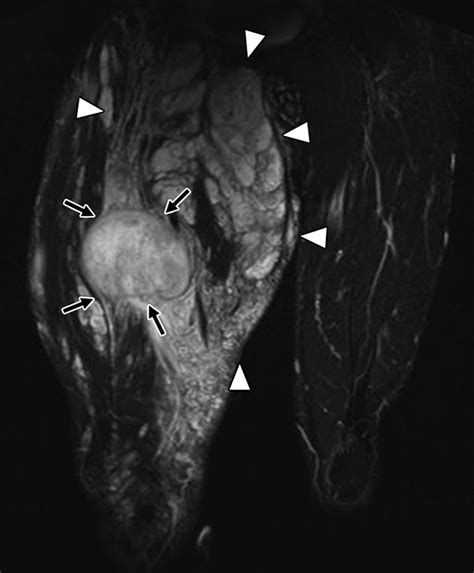

Magnetic Resonance Imaging (MRI) Provides high-resolution images of soft tissues, ideal for visualizing nerves.

• nerve sheath tumor radiology